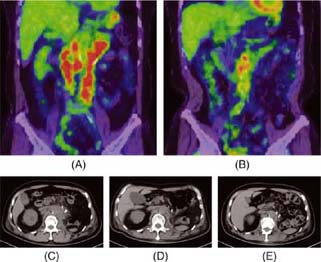

To assess the metabolic activity of HLRCC-associated RCC, fluorodeoxyglucose–positron emission tomography (FDG-PET) was performed. It showed strong accumulation in para-aortic lymph nodes, the left adrenal gland, and focally in the 12th thoracic to the third lumbar vertebrae. Metabolic tumor volume (MTV) and total lesion glycolysis (TLG) were 215.3 cm3 and 1042.5 g, respectively (Figure 4A). Axitinib was initiated following radiotherapy at 30 Gy in 10 fractions in combination with zoledronic acid to bone metastases, which achieved a partial response (Figure 4C, 4D). Nivolumab was started 7 months after starting axitinib. The patient had been in sustained partial response on nivolumab, with significant reductions in MTV and TLG of 15.8 cm3 and 112.5 g, respectively, at 8 months after the start of nivolumab (Figure 4B, 4E). However, bilateral adrenal metastases progressed 18 months after the start of the systemic sequential therapy. He re-started axitinib (progressive disease 10 months later), followed by everolimus (stable disease but discontinued due to hepatic and renal toxicities 2 months later) and re-challenge of nivolumab. He is alive with disease on nivolumab beyond slowly progressive disease 48 months after CN (58 months after the diagnosis of advanced kidney cancer).

Figure 4: FDG-PET before axitinib (A) and 8 months after nivolumab following 7-months of axitinib (B). Metabolic tumor volume (MTV) was defined as the tumor volume greater than 40% of standardized uptake value (SUV) max. Total lesion glycolysis (TLG) was calculated as MTV×SUVmean. MTV and TLG were calculated by using LIFEx package (www.lifexsoft.org). MTV/TLG are 215.3 cm3/1042.5 g (A) and 15.8 cm3/112.5 g (B). CT before axitinib (C), 6 months after axitinib (D), and 7 months after nivolumab (E).